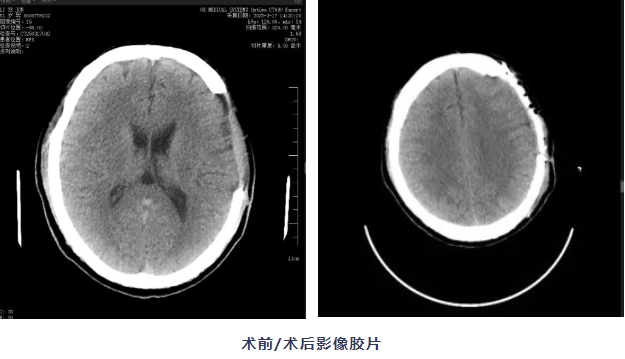

近日,我院神经外科团队为一名创伤性硬膜下血肿术后患者成功实施了一例特殊手术——PEEK颅骨修补术,让患者重新获得完整头型的同时,更帮助他找回正常生活的勇气。

张师傅(化名)是一名建筑工人,3个月前,他在工地意外受伤,经过紧急开颅手术保住了性命,但右脑侧留下了一个凹陷。每次出门,张师傅都戴着帽子,又闷又热不说,还经常感到头晕耳鸣,性格也变得孤僻。为恢复颅腔完整性,提升生活质量,他于术后1月再次入院,我院专家会诊评估后,拟行颅骨修补手术。

“患者的情况,就像手机少了保护壳,大脑缺少了防护。”神经外科主任邱斌表示,传统颅骨修补材料存在导热性强、术后异物感明显等问题,好比金属板,冬天冰凉夏天发烫,还容易变形。本次手术拟采用的PEEK(聚醚醚酮,一种高级医用塑料),具有高度生物相容性、精准三维塑形、隔热抗感染等优势,与人体骨骼弹性模量接近,可避免应力性损伤,同时通过3D打印技术“量体裁衣”,制作出的"头骨补丁"与患者头型吻合。此外,该材料性能稳定,可降低术后并发症风险。

在手麻科、放射科等多学科配合下,邱斌主任团队凭借丰富的颅脑手术经验,像拼乐高积木一样,精准将这个乳白色的"头骨拼图"嵌入缺损部位,术中出血少、操作时间短,颅骨外形自然对称。